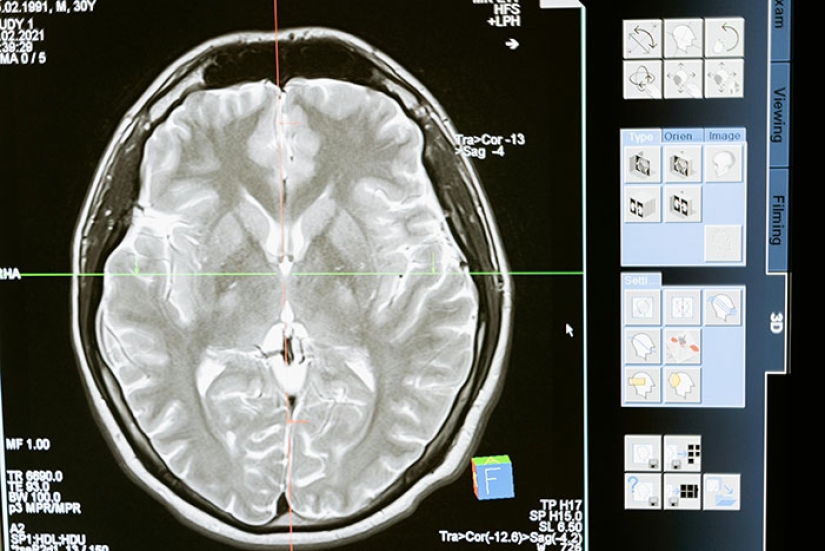

Brain aneurysms can happen at any time, to anyone. No matter what age you are, or even how healthy you are, if you are currently alive, you have a chance of getting a brain aneurysm. When you do get one, there's a 50 % chance you'll just die immediately. Like, you'd be alive one minute, and then lying on the floor unconscious the next minute. Are the chances of actually getting a brain aneurysm at any random moment low? Yes, but it's still not 0.

Scientific litterature conclusion on alzheimer's disease and other neurodegenerative diseases in general is that the diseases start decades before the first obvious symptoms and that we need to treat them at this stage. When you exhibit obvious symptoms, it's too late, your brain is already mush.

If you get diagnosed with Alzheimer's at 65, you had the disease since your early 40s at least. And you experienced very mild symptoms but didn't notice it. And your brain fought like hell to compensate for the deficit. When you get diagnosed, your brain is already very severely damaged and will never recover from the deficit.